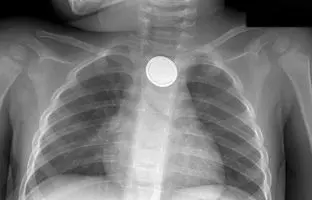

• توصیه‌ها برای نجات کودکانی که باتری دکمه‌ای بلعیده‌اند! پزشکی و سلامت

توصیه‌ها برای نجات کودکانی که باتری دکمه‌ای بلعیده‌اند!